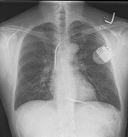

Cardiomyopathy is a group of diseases that affect the heart muscle.<br />Types of cardiomyopathy include 1-hypertrophic cardiomyopathy, 2- dilated cardiomyopathy, 3- restrictive cardiomyopathy, 4-arrhythmogenic right ventricular dysplasia<br />In hypertrophic cardiomyopathy the heart muscle enlarges and thickens its cause in inheritid. In dilated cardiomyopathy the ventricles enlarge and weaken its causes mainly are secondary to viral infection, alcohol and coronary heart disease but inheritance are also registered . In restrictive cardiomyopathy the ventricle stiffens. Its causes are mainly amyloidosis, hemochromatosis, and some cancer treatments.<br />Symptoms of cardiomyopathies may include fatigue, swelling of the lower extremities and shortness of breath after exertion. Additional symptoms of the condition may include arrhythmia, fainting, and dizziness, Those affected are at an increased risk of sudden cardiac death.<br />Treatment may include suggestion of lifestyle changes to better manage the condition. Treatment depends on the type of cardiomyopathy and condition of disease, but may include medication (conservative treatment) or iatrogenic/implanted pacemakers for slow heart rates, defibrillators for those prone to fatal heart rhythms, ventricular assist devices (VADs) for severe heart failure, or ablation for recurring dysrhythmias that cannot be eliminated by medication or mechanical cardioversion. The goal of treatment is often symptom relief.<br /><br />COVID-19 Cardiovascular complications are thought to be a combination of direct viral injury and the host's immune response resulting in vascular inflammation and myocardial inflammation , Cardiomyopathies (CMPs) which resulted from heart muscle involvement, are among the main causes of adolescent sudden death and heart failure.<br />un fortunately heart transplantation still away from many patients and doctors.<br /><br />